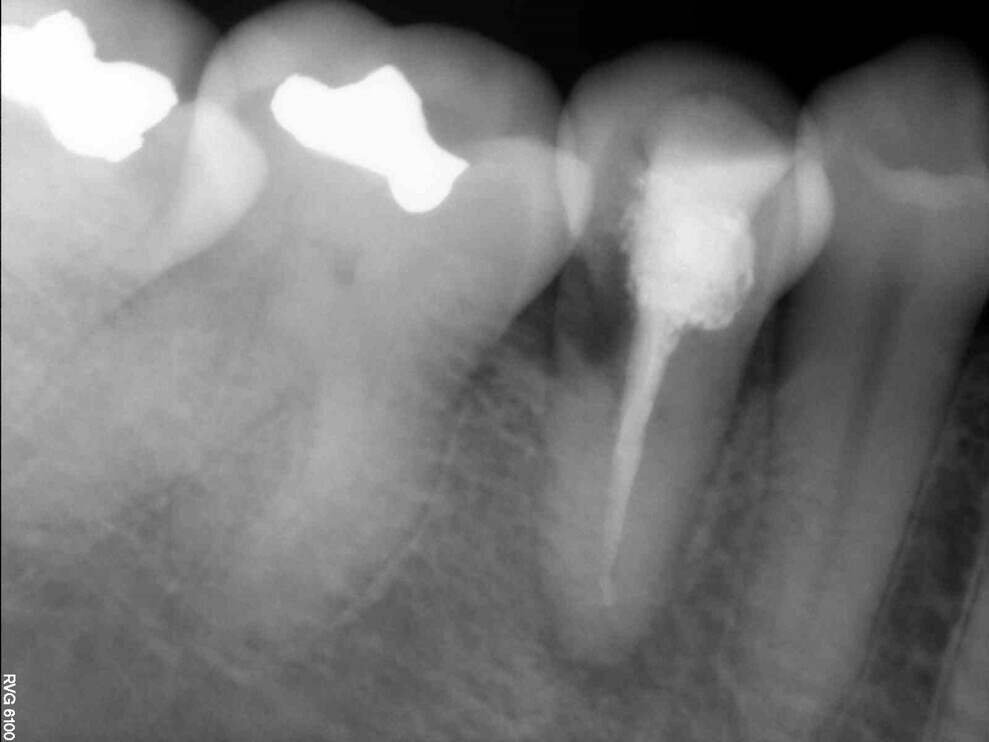

Fig. 7: The periapical radiograph at six months showed almost complete healing and no signs of apical pathosis.

After six months, another CBCT scan was performed to evaluate healing. Almost complete resolution of the periapical lesion was observed (Fig. 6). The intra-oral situation also looked good, and there were no signs of apical pathosis on the periapical radiograph, which also showed almost complete healing (Fig. 7). The tooth remained asymptomatic.